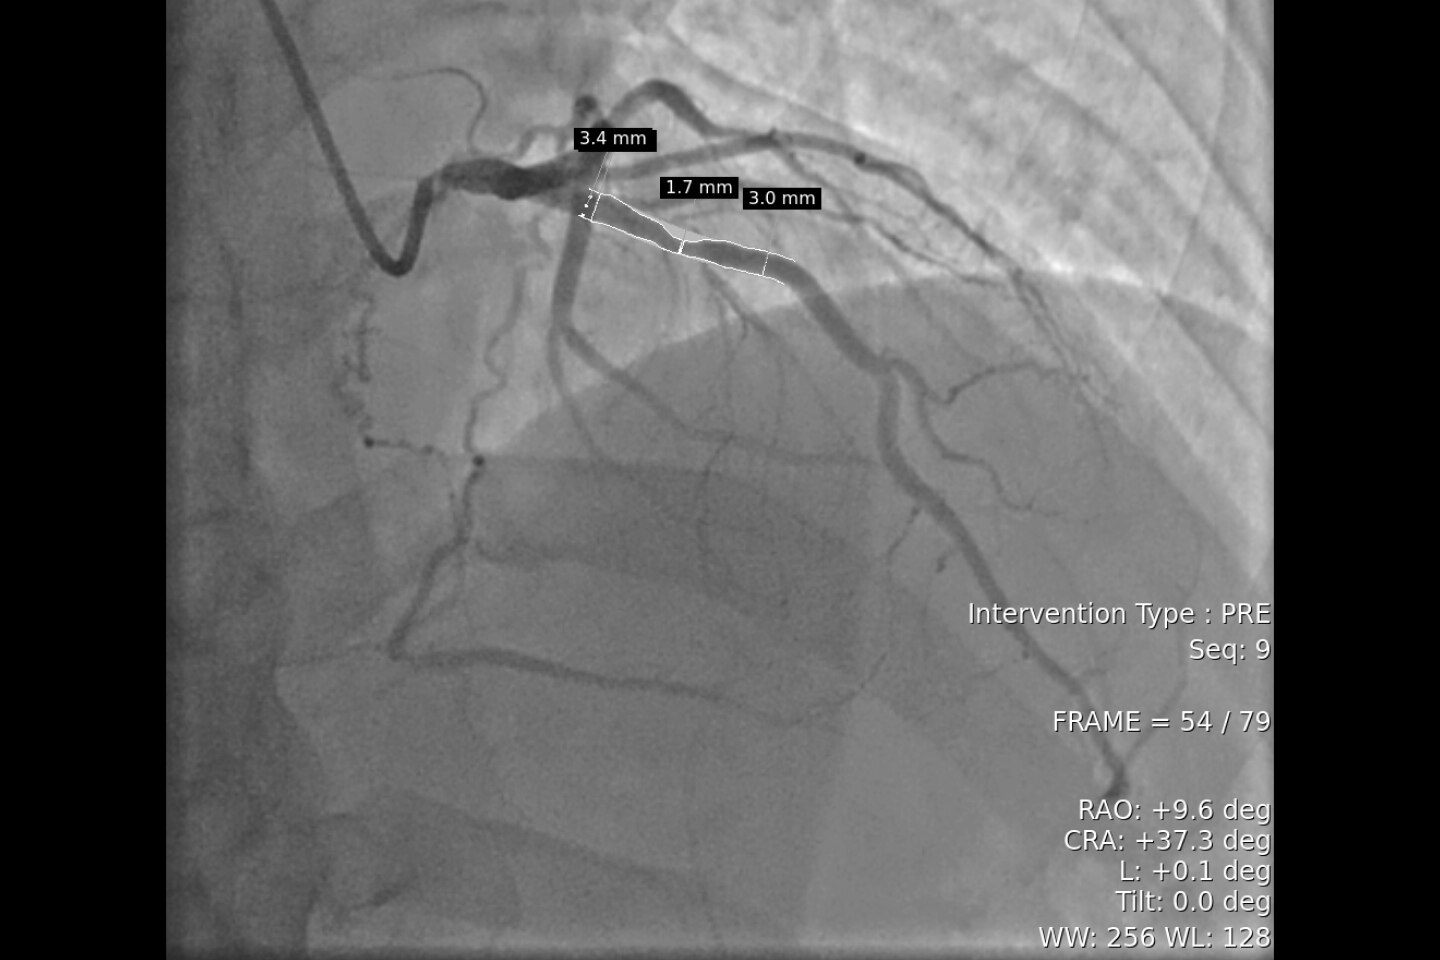

Rilevamento automatico dell'occlusione dei grandi vasi (LVO) con tecnologia StrokeSENS²

• StrokeSENS LVO² usa l'intelligenza artificiale per riconoscere le occlusioni dei grandi vasi (LVO) con l'angiografia TC.

• Se viene rilevata una LVO, la LVO sospetta viene scritta nell'immagine DICOM di input (TCA o 1ª fase della mCTA) e i risultati vengono automaticamente inclusi nell'e-mail di notifica, per informare l'équipe dedicata che si tratta di un caso urgente.